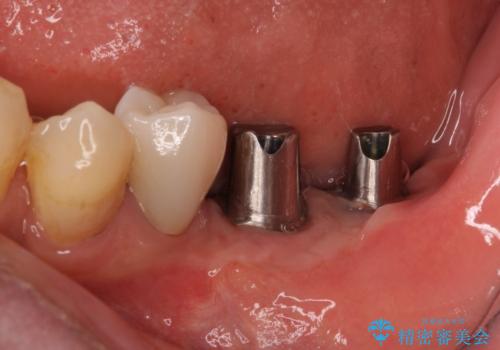

追加のインプラントと、歯肉移植による磨きやすい歯肉に改善

- 一度治療を終えたものの、奥歯へインプラントの追加を希望された患者様です。

最後臼歯部にインプラントを1本追加埋入し、2歯連結のクラウンにて補綴治療を行うこととしました。

インプラント埋入後、手前のインプラント周りの丈夫な歯肉(角化歯肉)が失われてしまったため、角化歯肉の移植を行うこととなりました。

十分な角化歯肉が獲得でき、清掃性の高い環境が達成されました。